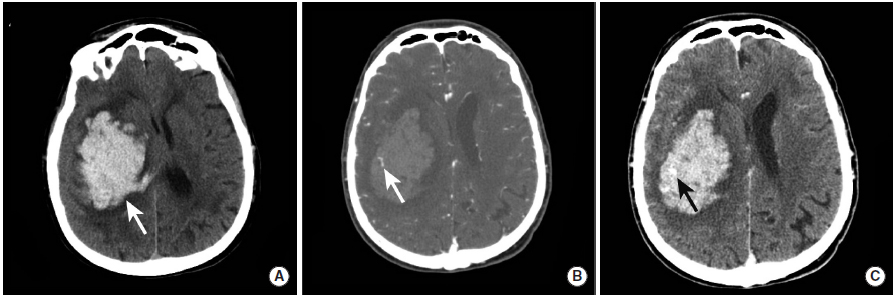

出血性脑实质挫伤

图5

本图显示了出血性脑实质挫伤随时间的演化过程。图A~C为接诊患者时进行的检查,图D~F为2小时之后的复查。患者左侧眶额叶和左前颞叶可见多发小出血灶。在后续成像中,挫伤导致的出血出现了扩大。

脑微出血

图6

本例患者接受了CT和MRI检查,以评估出血性实质性挫伤。与平扫CT(图A)相比,MRI的GRE(图B)和SWI(图C)序列显示的出血性挫伤(长尾箭头)更为显著。此外,GRE和SWI序列可见脑白质中的脑微出血(三角箭头)。

高血压引起的脑实质出血

图7

本例高血压性脑出血患者具有典型的“点状征”表现。

图A:CT平扫显示右侧基底节区大量脑出血(长尾箭头)。

图B:CTA扫描动脉期显示点状高密度影(长尾箭头),即“点状征”。根据“点状征”的定义,点状强化为血肿边缘与血管不相连的高密度灶。

图C:CTA扫描延迟期显示活动性出血灶中与图B相同位置的高密度影(长尾箭头)。

脑淀粉样血管病引起的脑实质出血

图8

本例患者的CT平扫(图A)、MRI的GRE(图B)和SWI(图C)序列显示右颞叶和枕叶的脑实质内出血(长尾箭头)。这种出血的典型表现是脑叶出血,并不限于动脉的供血区域。本例患者最终被诊断为脑淀粉样血管病。